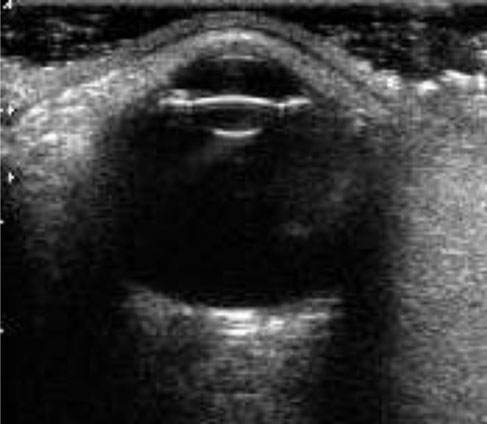

Fundus Kamera

Badanie fundus kamerą umożliwia dokładną ocenę dna oka, pozwala ocenić wygląd siatkówki i tarczę nerwu wzrokowego, dzięki czemu możemy diagnozować takie choroby jak dysplazje i retinopatie siatkówki, zmiany o charakterze zapalnym, ostrym i przewlekłym